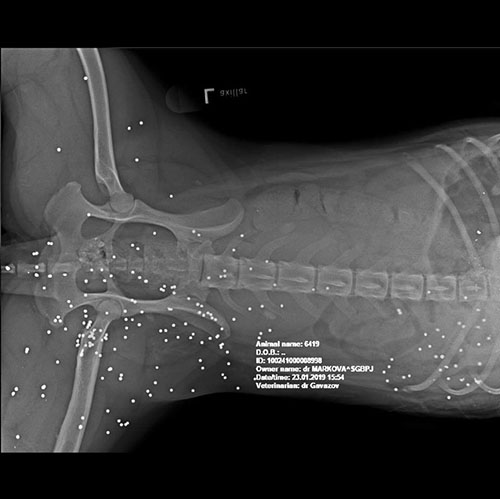

Vor 4 Jahren kam sie aus Ruse als Notfall zu uns. Sie hatte ca. 150 Schrotkugeln im Körper und war dadurch gelähmt. Sie wurde angeschossen und ihr Hundekumpel, mit dem sie auf Mäusejagd war, hat es nicht überlebt.

Der "Jäger" wurde angezeigt und bekam eine lächerliche Strafe für einen lebenslangen Pflegefall und einen Mord..